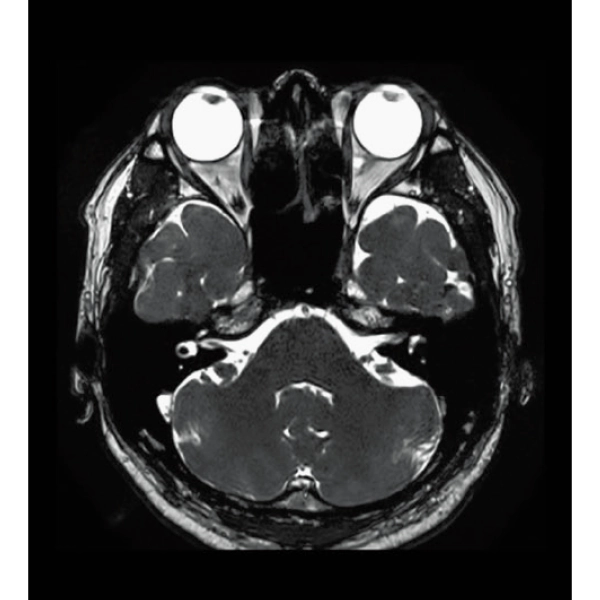

3D Balanced SARGE

with Phase Cycling,

0.93×0.70×1.0(0.5)mm, 1:44